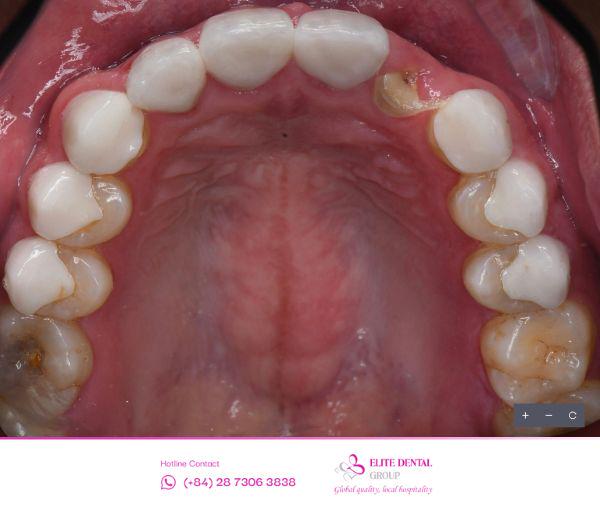

8 năm là một quãng thời gian đủ dài để những sai sót kỹ thuật nhỏ biến thành vấn đề y khoa nghiêm trọng. Cái giá của sự “cấp tốc” không chỉ là tiền bạc, mà là cả sức khỏe. Hàm răng sứ cũ đã gây sai lệch khớp cắn nghiêm trọng, khiến anh Kye phải sống chung với cảm giác mỏi cơ hàm kinh niên và những cơn đau đầu dai dẳng. Khớp cắn không chuẩn khiến lực nhai phân bố không đều, dẫn đến tình trạng ê buốt kéo dài, khiến việc ăn nhai không còn là niềm vui mà trở thành nỗi lo, đặc biệt khi đối diện với thức ăn dai hoặc cứng.

Tuy nhiên, điều tồi tệ nhất lại đến từ góc độ thẩm mỹ và công việc. Với vai trò Giám đốc thời trang của Anh Trai Say Hi, ngoại hình luôn cần sự hoàn hảo, nhưng hàm răng sứ cũ lại thiếu tự nhiên, màu sắc không hài hòa với tổng thể khuôn mặt. Đỉnh điểm là những lần răng sứ bị gãy đột ngột – hậu quả của chất lượng sứ kém và khớp cắn sai – khiến anh phải đối mặt với nỗi lo thường trực trong giao tiếp và công việc.

Sau khi chẩn đoán, bác sĩ chuyên khoa đã đưa ra chỉ định chính xác: Nhổ bỏ chân răng cũ đã gãy và không thể phục hồi được, sau đó tiến hành Cấy ghép Implant đơn lẻ để thay thế vĩnh viễn chiếc răng bị mất.

Kỹ thuật Nhổ Răng Hạn Chế Xâm Lấn: Việc nhổ bỏ được thực hiện với kỹ thuật tối thiểu xâm lấn để bảo tồn tối đa xương ổ răng.

Cắm Implant: Trụ Implant được cắm vào đúng vị trí của chân răng cũ bằng thiết bị hướng dẫn động Navigation. Đây là một kỹ thuật khó, đặc biệt ở vùng răng cửa, vì nó đòi hỏi sự khéo léo và chuyên môn cao để: